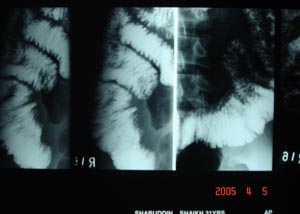

Barium follow through

For large intestine this is single contrast method. The barium forms a continuous column defining the diameter of the large bowel.